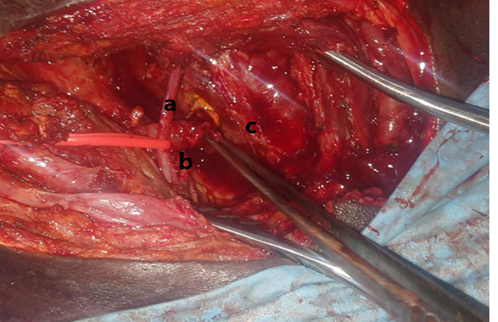

His renal function had normalised three days following transplant with serum urea and creatinine values of 5.4mmol/L and 96umol/L respectively. Few days following the removal of the double j stent, he had a progressively increasing peri-allograft collection, worsening pain, and swelling over the transplanted area with oliguria and drainage from the surgical scar. Initial conservative treatment of the urine leak by urethral catheterization and percutaneous drainage of the collection under image guidance were unsuccessful. He has a re-exploration with secondary uretero-neocystostomy and is doing very well.